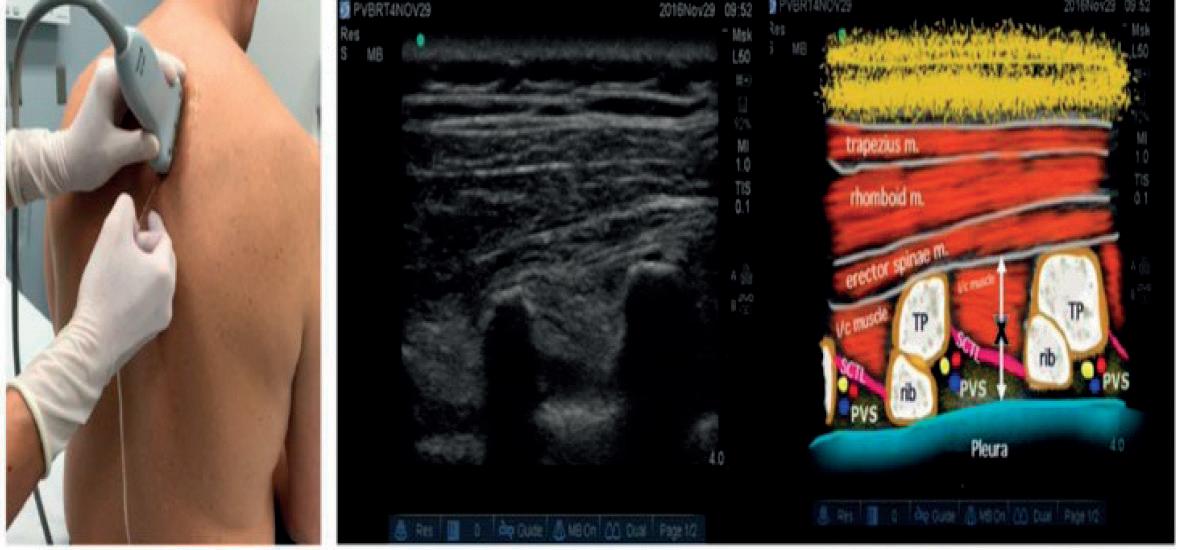

Είναι σημαντικός ο προεγχειρητικός έλεγ

χος του αναπνευστικού συστήματος από

τον πνευμονολόγο για τον καθορισμό ασθενών υψηλού κινδύνου και την πρό ληψη αυτών των λοιμώξεων. Είναι επίσης σημαντική για την πρόληψη των λοιμώ ξεων αυτών η σύμπραξη άλλων ειδικο τήτων, όπως π.χ φυσικοθεραπευτών για την εφαρμογή τεχνικών προφυλακτικής έκπτυξης πνεύμονα, αναισθησιολόγων για την αποφυγή γενικής αναισθησίας όπου αυτό είναι εφικτό αλλά και χει ρουργών για την εφαρμογή συγκεκρι μένων χειρουργικών τεχνικών, ώστε να ελαχιστοποιηθεί η πιθανότητα ανάπτυξης λοίμωξης.